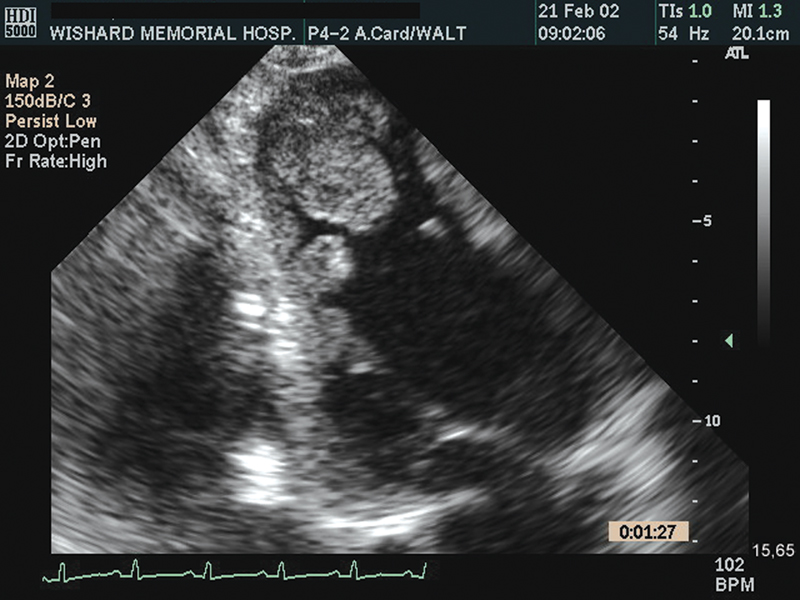

فحوصات تشخيصية لبعض امراض القلب والشرايين التاجية